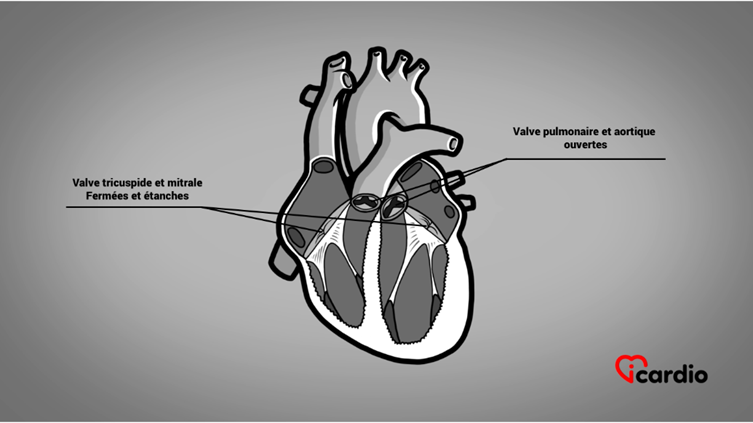

2 de ces valves cardiaques sont la valve pulmonaire et la valve aortiqueLa valvule aortique est située entre le ventricule gauche et l’aorte. C’est l’une des quatre valves du cœur. >>. Elles sont situées à la base des gros vaisseaux, soit à la sortie des ventriculesLes ventricules sont les 2 cavités inférieures du cœur. Ils sont plus musclés que les oreillettes; ils servent à propulser le sang pour assurer la circulation dans tout le corps. >>.

On les appelle valves tricuspides parce qu’elles sont formées de 3 cupules reliées à l’anneau. Elles séparent respectivement l’artère pulmonaire du ventricule droit et l’aorte du ventricule gauche.

Lorsque les ventriculesLes ventricules sont les 2 cavités inférieures du cœur. Ils sont plus musclés que les oreillettes; ils servent à propulser le sang pour assurer la circulation dans tout le corps. >> se contractent, la pression générée par le muscle repousse le volume sanguin vers le haut, fermant ainsi les feuillets.

Les feuillets sont retenus par des cordages qui les empêchent de se replier dans les oreillettesLes oreillettes sont les deux cavités supérieures du cœur. Elles agissent comme des réservoirs du sang qui ira remplir les ventricules. >>.

Ainsi, la seule voie de sortie du sangLe sang est composé de globules rouges, de globules blancs, de plaquettes et de plasma. Les globules rouges sont responsables du transport de l’oxygène et du dioxyde de carbone. Les globules blancs constituent notre système de défense >> se fait à travers la valve pulmonaire, à droite, et la valve aortiqueLa valvule aortique est située entre le ventricule gauche et l’aorte. C’est l’une des quatre valves du cœur. >>, à gauche.